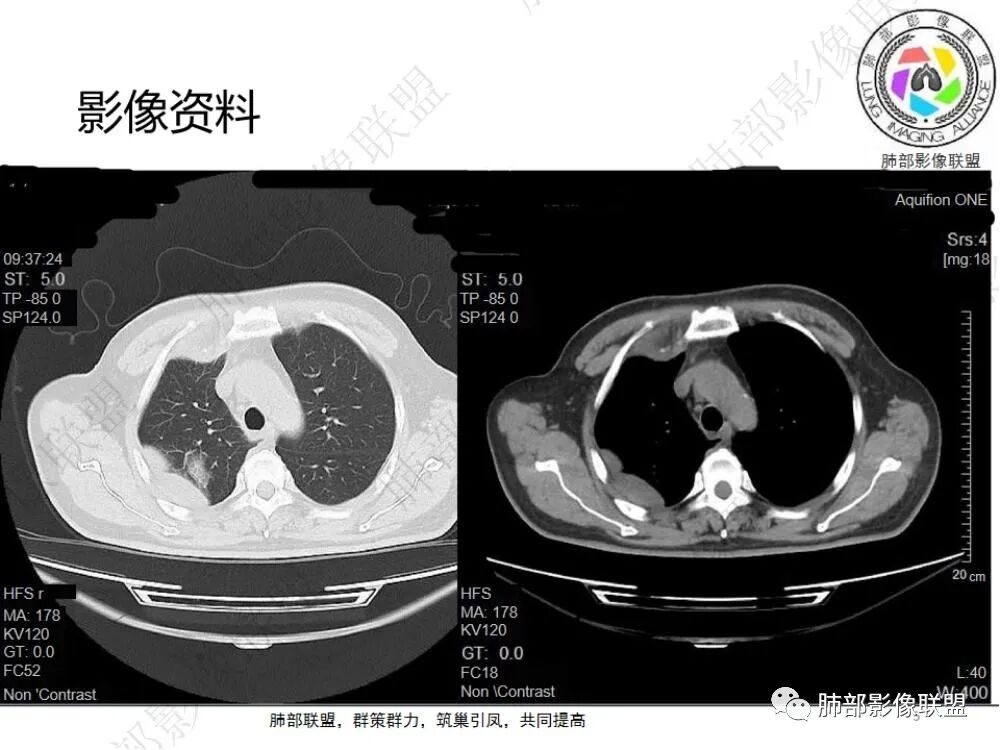

2.影像显示右肺上叶后段及右肺下叶较大范围实性密度为主片状影,边界可分辨,密度较均匀,隐约见小范围低密度(可疑液化区),未见钙化及气囊影。

3.左肺上叶见小片影,边界不清,实性及磨玻璃混合密度。

4.右侧胸腔积液,多包裹局限。

5.纵隔见轻度增大淋巴结。

6.一周后复查变化较为明显。肺部实变影有所吸收,但胸腔积液增加明显,包裹于侧胸壁、纵隔旁及叶间裂。注意右肺下叶因积液推压明显(可惜未能提供薄层图片及矢状位图片)。